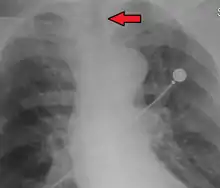

Ideally, at least one of the methods utilized for confirming tracheal tube placement will be a measuring instrument. Waveform capnography has emerged as the gold standard for the confirmation of tube placement within the trachea. Other methods relying on instruments include the use of a colorimetric end-tidal carbon dioxide detector, a self-inflating esophageal bulb, or an esophageal detection device.[35] The distal tip of a properly positioned tracheal tube will be located in the mid-trachea, roughly 2 cm (1 in) above the bifurcation of the carina; this can be confirmed by chest x-ray. If it is inserted too far into the trachea (beyond the carina), the tip of the tracheal tube is likely to be within the right main bronchus—a situation often referred to as a "right mainstem intubation". In this situation, the left lung may be unable to participate in ventilation, which can lead to decreased oxygen content due to ventilation/perfusion mismatch.[36]